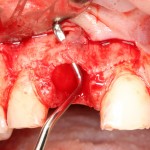

Затем, мы готовим лунку и проверяем позиционирование импланта:

После чего аугментируем лунку. Для упаковки Bio-Oss Collagen очень удобно использовать аналоги имплантов:

Устанавливаем имплантат XiVE (Dentsply Implants):